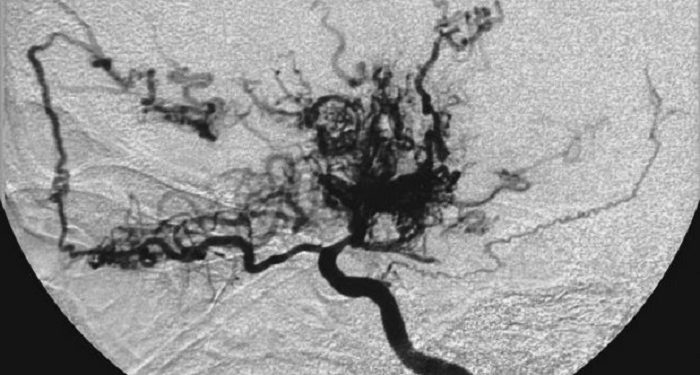

Namun, pembuluh-pembuluh ini tidak sekuat atau seefisien pembuluh utama yang terganggu. Dalam hasil angiogram, pembuluh darah baru ini terlihat seperti kepulan asap, yang dalam bahasa Jepang disebut moyamoya.

Itulah asal mula penamaan penyakit ini. Menurut Cleveland Clinic, penyakit Moyamoya paling sering ditemukan pada anak-anak usia 5 hingga 10 tahun dan orang dewasa usia 30 hingga 50 tahun.